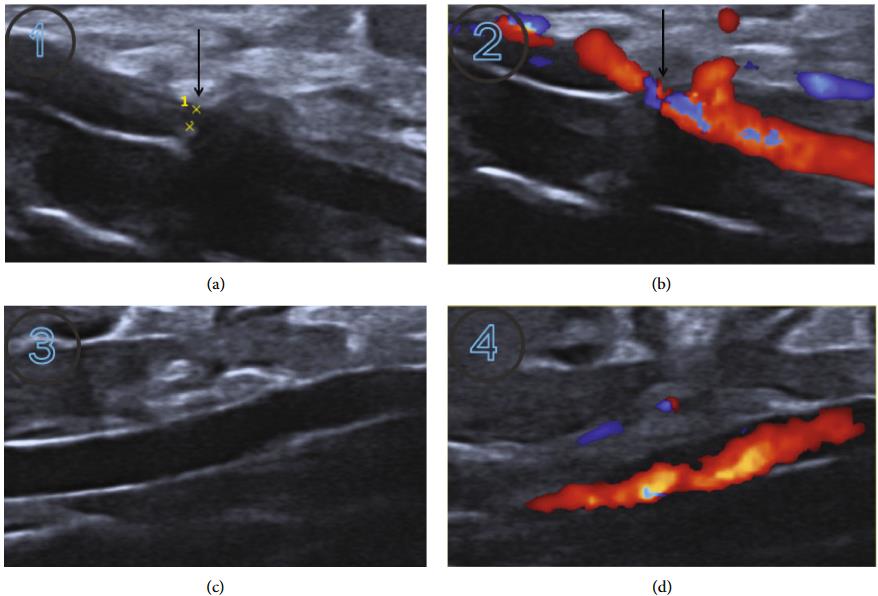

Fig.2 Post-operation analysis of the abdominal aortic contraction-induced HF model.1

In this study, a stable and reproducible rat HF model was successfully established. The study confirmed successful modeling at 10 weeks post-operation, evidenced by significant changes in echocardiographic parameters, increased cardiac and left ventricular mass indices, characteristic cardiac pathological staining, and elevated serum brain natriuretic peptide (BNP) levels, affirming its utility for comprehensive HF research.